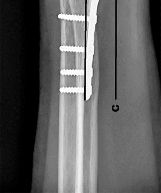

Question 7:

A 45-year-old trauma patient sustains an intra-articular distal femur fracture. Advanced imaging identifies a coronal plane fracture of the lateral femoral condyle (Hoffa fragment). Biomechanical studies suggest which of the following screw orientations provides the most rigid fixation for this specific fracture pattern?

Correct Answer: Posteroanterior oriented lag screws

Explanation:

A Hoffa fracture is a coronal plane fracture of the femoral condyle, more commonly affecting the lateral condyle. Biomechanical studies have demonstrated that posteroanterior (PA) directed lag screws provide superior stability and higher load to failure compared to anteroposterior (AP) directed screws. While AP screws are often used clinically due to ease of placement via an anterior approach, PA screws are biomechanically advantageous because they enter through thicker cortical bone posteriorly and are directed perpendicular to the fracture plane.